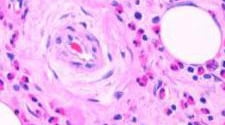

Низкий уровень лейкоцитов в крови называется лейкопенией. Так как лейкоциты в организме отвечают за защитные функции, то их низкий уровень приводит к снижению иммунитета.

Читать »Почему лейкоциты в крови повышены: причины и лечение

Повышение белых кровяных телец в крови (лейкоцитов) называется лейкоцитозом.